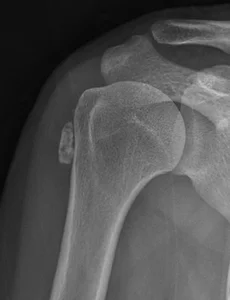

Shoulder61 Proximal humerus fracture Proximal humerus fracture65 years old female patientTripping over a rope Pre-op Post-op Materials : Philos plate(AO synthes) & 2.4 mm mini-plate(AO synthes) 제일 처음 cortical screw를 고정할 위치에 Fx. line이 존재하여미리 2.4 mm mini-plate 로 OR & fixation을 하여어느 정도 stability를 만든 후, Philos plate를 apply 함. 2026. 1. 1. Comminuted clavicle mid-shaft fracture Comminuted clavicle mid-shaft fracture36 years old male patient Pre-op Post-op Materials : AO synthesnew version, 2.7 mm clavicle platelag screw, 2.4 mm mini-screw 쇄골 골절을 쉽게 생각하면 절대 안됩니다 2025. 6. 23. Humerus surgical neck fracture Humerus surgical neck fracture 52 years old female patientSlip down injury in the bath room Pre-op Post-op 2024. 8. 20. Humerus neck fracture(ORIF) Fx humerus neck Lt. 35 years old male patient 자전거 타고 가다가 차와 충돌하여 LOC (+) Pre-op Post-op Product : AO synthes (Philos plate)Delto-pectoral approach 하여 biceps tendon의 just lateral에약간 비스듬히 Philos plate를 대면 정확한 고정이 이뤄집니다. 2024. 6. 22. 어깨의 인대 손상 격렬한 운동을 하다 보면 어깨 관절을 다치기가 아주 쉽습니다. 그러면 어깨 관절에 피하 출혈(멍듦)이 생기기도 합니다. Skin bruise of shoulder joint 어깨 관절의 인대는 상당히 강하며 뼈와 뼈를 연결하는 구조물이기 때문에 우리 몸속 깊숙히 있습니다. 어깨 관절의 인대(ligament) 인대 손상의 확인은 MRI 검사로 합니다. 2021. 11. 6. Frozen shoulder(동결견) 정상적인 어깨 관절은 견갑-흉곽 운동(Scapulo-thoracic motion)에 의해서 복합적으로 이뤄지게 됩니다. 어깨 통증으로 평소 사용하는 앞쪽 근육이 아닌 잘 사용하지 않는 어깨 뒷쪽 근육부터 굳기 시작을 합니다. 그래서 처음에는 어깨의 내회전(열중 쉬어 자세)이 안됩니다. '동결견'은 어떤 이유(당뇨, 경추부 추간판 탈출증, 골절 등)로 인해 '어깨 관절의 운동 범위가 감소한 경우'로 정의 합니다 '동결견'의 병태 생리는 '어깨 관절의 비화농성 염증(non-pyogenic inflammation) 및 관절막의 섬유화(fibrosis)' 입니다 최근에는 '경추부 추간판 탈출증'으로 인한 '이차성 동결견'이 증가하는 양상을 보이고 있습니다 '오십견'이라는 병명은 정확한 병명은 아닙니다 '동결견'.. 2021. 1. 10. Proximal humerus fracture(Hemi-arthropalsty) Proximal humerus fracture 88 years old female patient with severe OA change Pre-op Post-op 2020. 2. 2. Cuff tear arthropathy shoulder Rt. Cuff tear arthropathy shoulder Rt. 70 years old male patient 회전근개 파열 후 오랜 시간이 지나 '관절염'이 발생한 경우입니다. 2019. 11. 18. Calcific tendinitis shoulder both Calcific tendinitis shoulder both 46 years old female patient 2019. 9. 4. 이전 1 2 3 4 ··· 7 다음